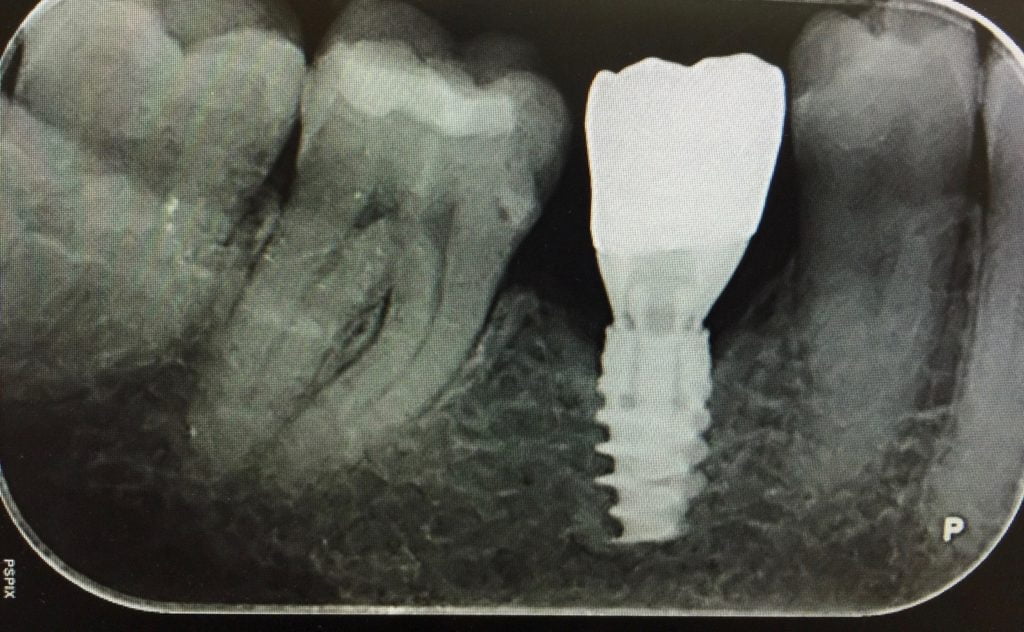

Our recommendation is if the tooth is too expensive to repair, then replace it with an implant crown.

Placing an implant is less painful than taking a tooth out.

We drill a small hole through the gum into the bone. Bone does not contain nerves so you don’t get any pain. The bone grows around the implant.

The Titanium implant rarely fails as opposed to deep fillings or root canal treatment.

Within 3 months you can have crowns attached to the implants and your smile is restored. The crowns are attached with screws and no messy glue. The teeth are also easy to floss and to keep clean.

If you ever get a porcelain fracture, the dentist can unscrew the crown and get it repaired.